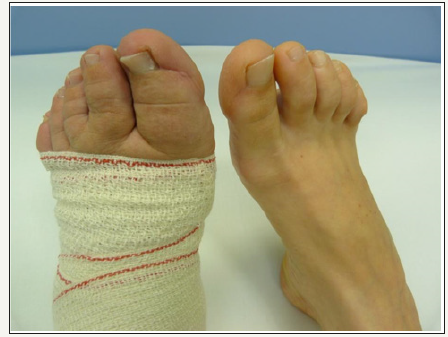

Within the family there were no problems with varicose veins. At admission, on the shin on the right there were extensive stem varicosities, pre-tibial and perimalleolar oedema. Pulsations were bilaterally well tangible at full range, trophic changes of the skin and adnex were not present. In the sacral region there was haemangioma of the size of 10x10cm (Figure 5). The whole left lower limb was thicker by 3-4cm. The left foot was significantly smaller than the right one, with skeletal malformation (Figure 6).

Figure 6:Deformities and changed configuration of the left foot.